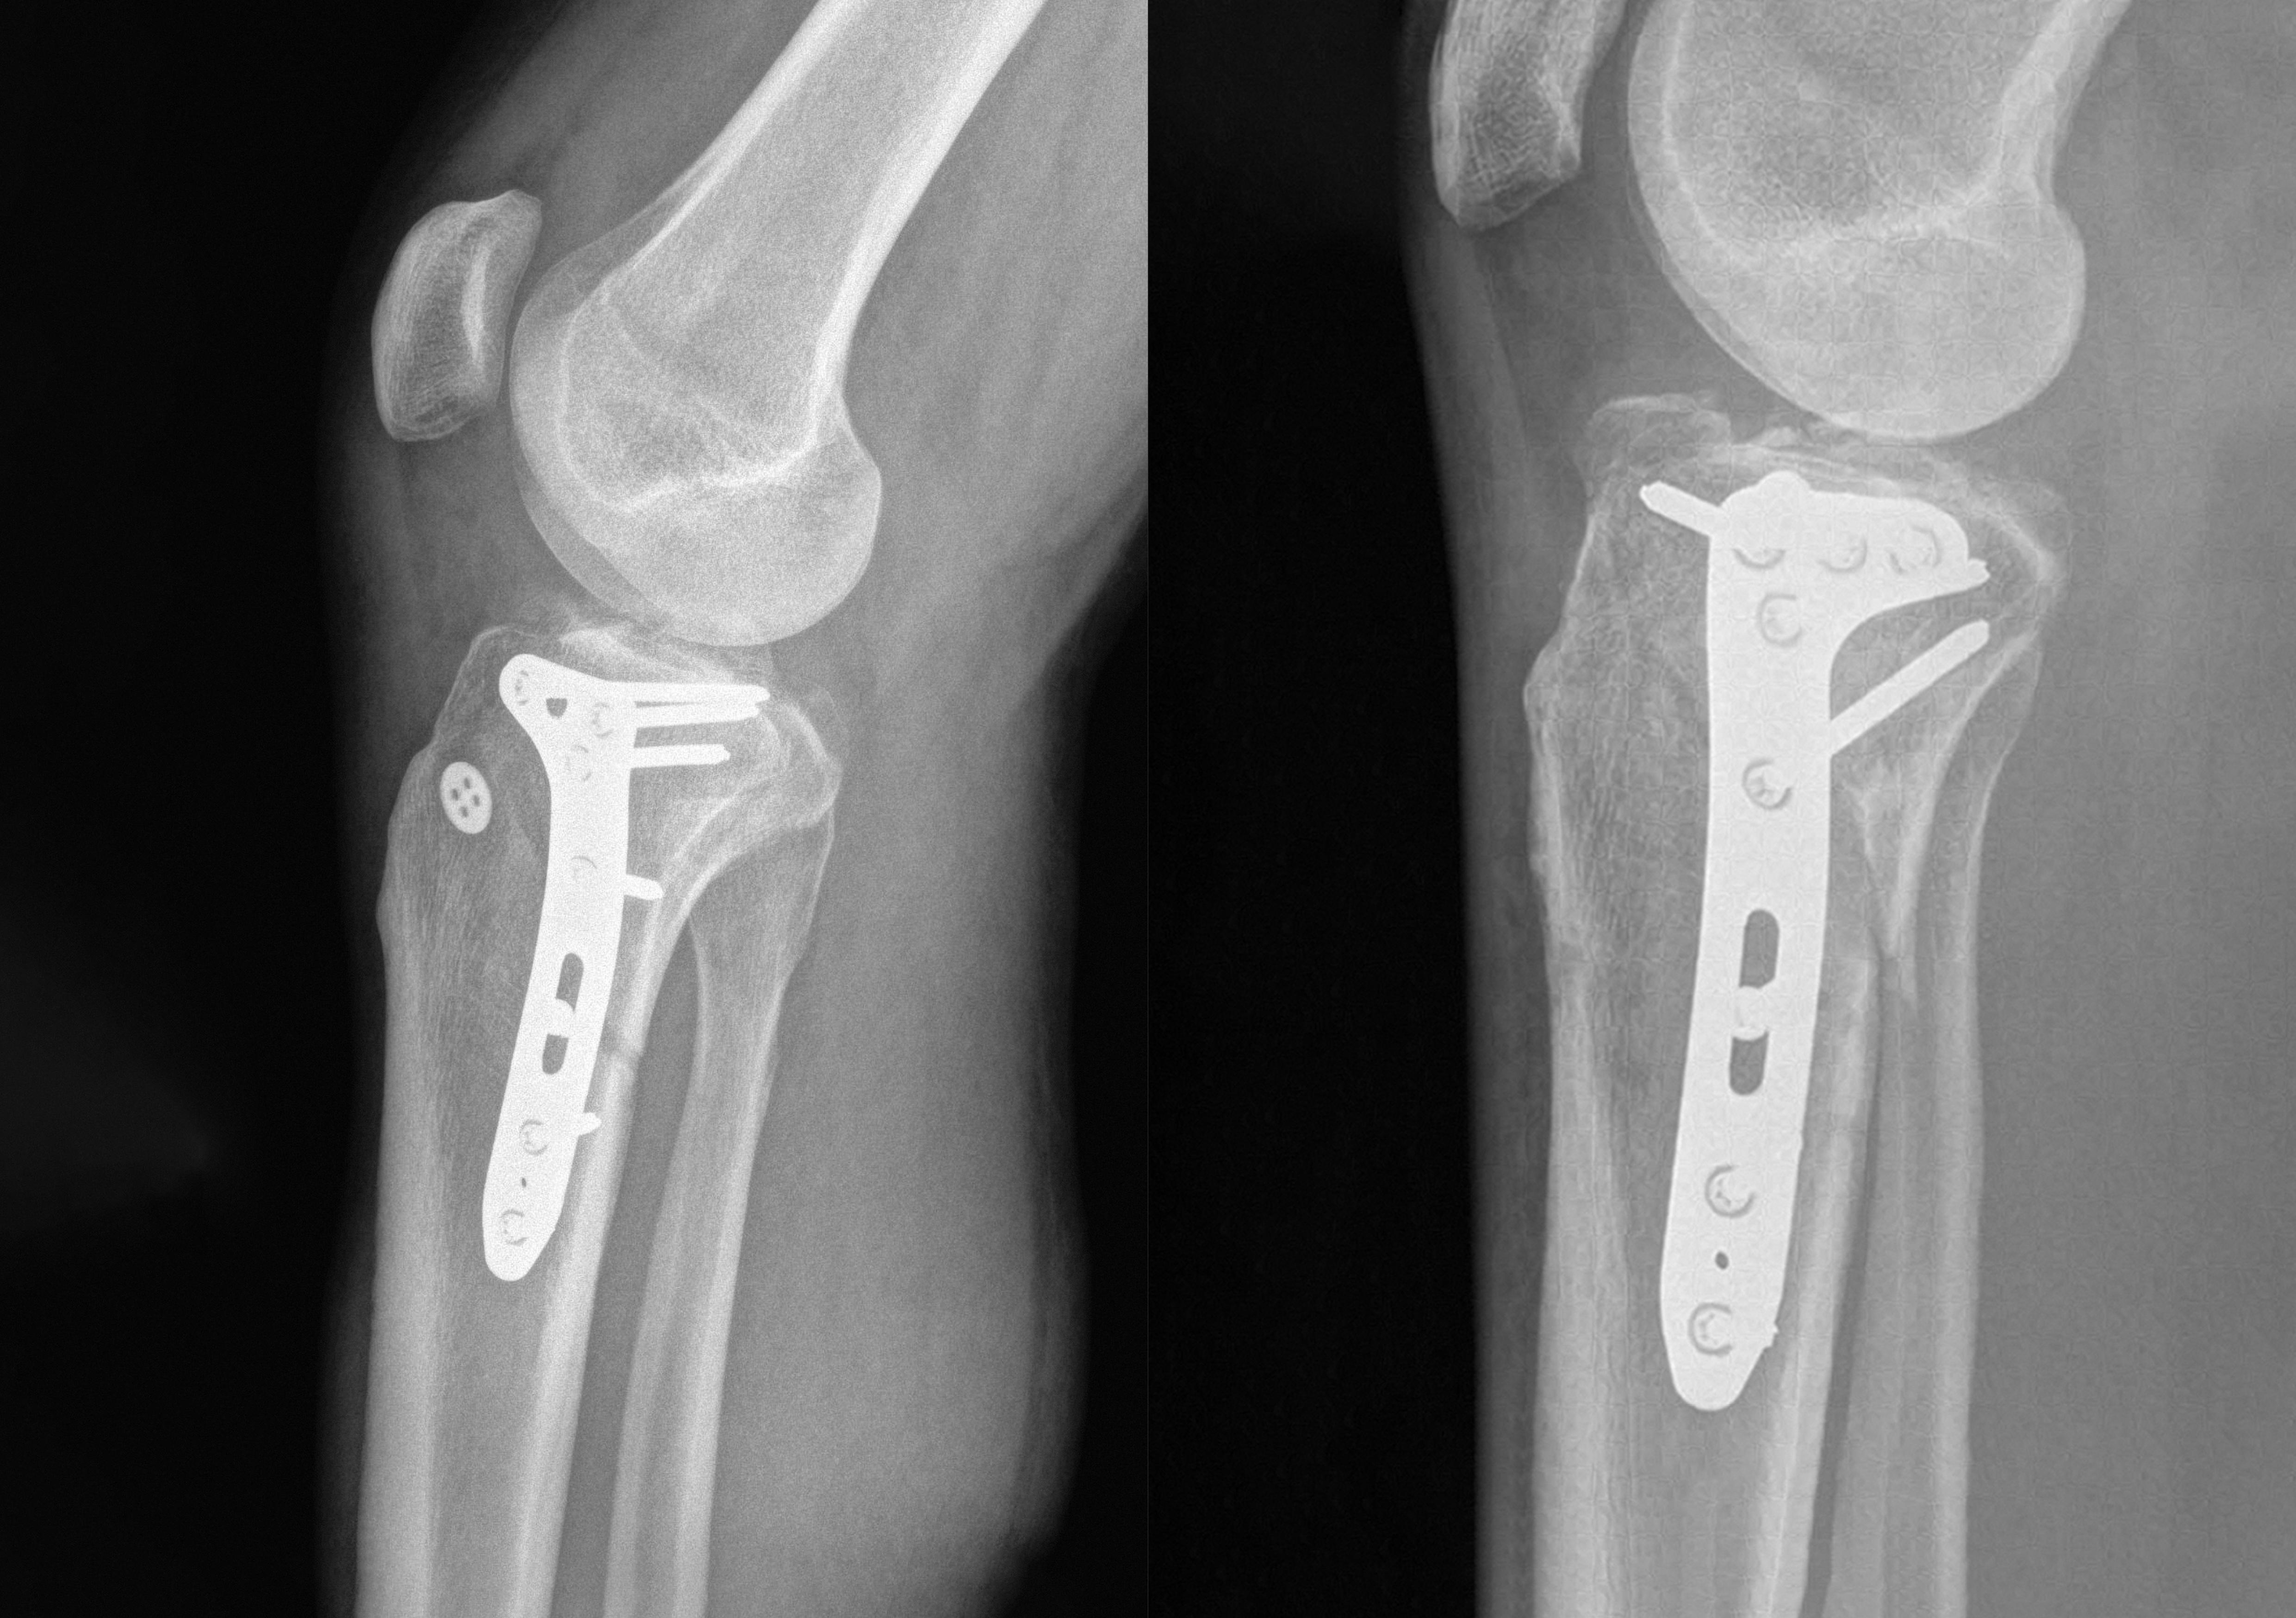

POYA CLINICAL CASES: MONOTRAUMA OF THE TIBIAL PLATEAU AFTER SKIING ACCIDENTS

We present two cases featuring our POYA 3.5mm Medial Proximal Tibia Plate.